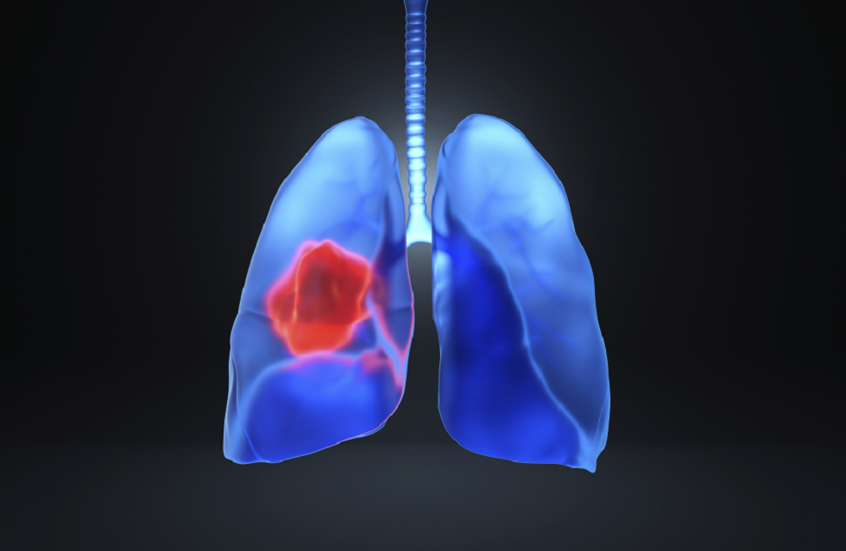

الوقت - كشف باحثون في مركز MD Anderson للسرطان بجامعة تكساس أن الالتهاب قد يكون سببا رئيسيا في ظهور المراحل المبكرة من سرطان الرئة.

ومن خلال إنشاء خرائط بصرية خلوية وجزيئية عالية الدقة لسرطان الرئة قبل وأثناء تطوره، تمكن الباحثون من تتبع تطور المرض في مراحله المبكرة وفهم الديناميكيات الجزيئية للخلايا السلفية للسرطان.

وأوضح الدكتور همام كدارا، أستاذ علم الأمراض الجزيئي الانتقالي: "وجدنا أن الخلايا المبكرة المسؤولة عن سرطان الرئة تتواجد في مناطق ذات التهاب شديد، تحيط بها خلايا محفّزة للالتهاب. واستهداف الالتهاب عبر تحييد محفّز يسمى IL-1B يقلّل من هذه الخلايا السلفية للسرطان. عملنا يمهد الطريق لاستراتيجيات جديدة لاعتراض المراحل المبكرة من المرض وتحسين حياة المرضى".

وتوفر خرائط التحليل المكاني للنسخ الجيني تمثيلا مرئيا لمكان وكيفية التعبير الجيني داخل العينات. ويتيح توصيف الخلايا والجينات في الآفات السلفية — تغيّرات في الأنسجة قد تتحول إلى سرطان — تحديد أهداف محتملة للتدخل المبكر.

وأنشأ الباحثون خرائط تحليل مكاني للنسخ الجيني لـ 56 آفة سلفية بشرية وعينات من سرطان الرئة المتقدّم من 25 مريضا، وتم التحقق من صحة النتائج باستخدام مجموعة مستقلة شملت 36 آفة من 19 مريضا، شملت 486519 بقعة و5.4 مليون خلية للتحليل.

أظهرت الدراسة أن مناطق الالتهاب في الآفات السلفية تحتوي على خلايا سنخية مرتبطة بالأورام، وتكون أكثر نشاطا وانتشارا في المراحل المبكرة من تطور السرطان. كما لوحظت هذه المناطق الالتهابية أيضا في النماذج المخبرية، ما يشير إلى أن الالتهاب فيها قد يكون عاملا مباشرا في ظهور الأورام.

وتشير النتائج إلى أن استهداف الالتهاب، سواء بمفرده أو مع العلاج المناعي، قد يمثل استراتيجية واعدة لاعتراض سرطان الرئة في مراحله المبكرة وتحسين فرص النجاة للمرضى.